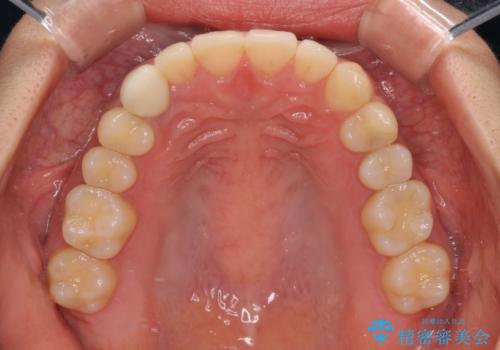

- 下顎の八重歯を気にして来院された患者様です。

マウスピース矯正でもワイヤー矯正でも対応可能であり、マウスピースによる治療を希望されたため、インビザラインを用いることとしました。

下顎前歯にデコボコが集中していたため、顎間ゴムによる後方移動とIPR(歯と歯の間を削ること)により歯列を整えることとしました。

しっかりとマウスピースを装着してくださったおかげで、スムーズに治療を終えることができました。